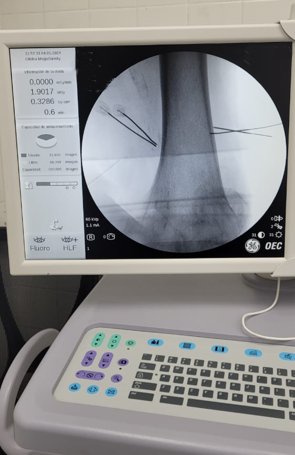

Por la morbimortalidad de la cirugía, se procede a realizar en Tidol un tratamiento con radiofrecuencia, debido al dolor intenso que le impedía la marcha.

Luego del procedimiento, el paciente deja de tomar los calmantes que se encontraba tomando para el dolor intenso y mejora su patología dolorosa.